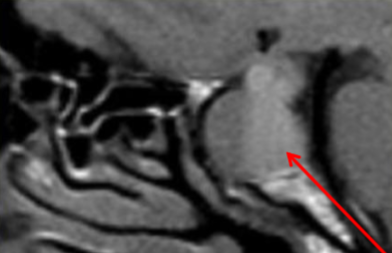

snowman configuration

what is the classic MRI sign of a pituitary macroadenoma on MRI?

snowman (pituitary macroadenoma)